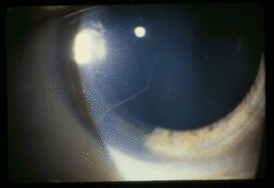

Видны нервные волокна роговицы у 27-летней пациентки с синдромом МЭН типа IIb

- другие частые проявления МЭН типа IIb: марфаноподобная внешность, прогерия, воронкообразная деформация грудной клетки, утолщение нервов роговицы, ганглионевромы желудочно-кишечного тракта, мегаколон. Утолщение нервов роговицы иногда наблюдают и при МЭН IIa.